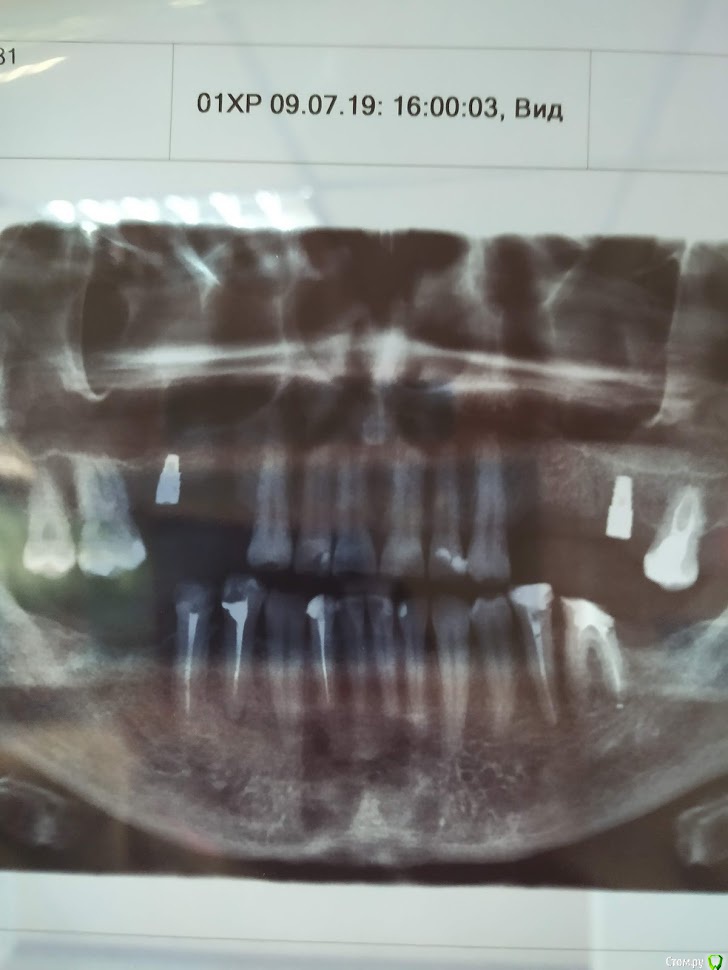

Валдемар Опубликовано 29 августа, 2019 Поделиться Опубликовано 29 августа, 2019 Добрый день,Уже был здесь, но прошлые явки и пароли забыл.12.04 операция 4 импланта20.04 вылез первый15.05 вылез второй26.08 удален 3ий28.08 удален 4ыйПотрачено 100тр, время и нервы. Возвращено 7200 за 2 импланта, за 2 которые удаляли деньги не вернули, так как не было показаний. А то что голова болит, переносица, лоб - ет не от этого. Удалил и всё прошло, кстати.Вопрос:1). Справа десны (кости) реально меньше чет слева. Что с этим делать. Как сделать чтобы кости хоть немного прибавилось? Без имплантации, просто кость с десной нарастить.2) 100% неприживаемости - ето как? Диабет, спид, гепатит по диспансаризации сдавал - отрицательно. Какие мои действия теперь? по новой имплантироваться и если опять не приживется, опять по новой? Ссылка на комментарий

Валдемар Опубликовано 31 августа, 2019 Автор Поделиться Опубликовано 31 августа, 2019 Я снимок после удаления не делал, но у меня реально справа десна тоньще раза в два. Там воспаление месяца два шло. В имплантацию больше не верю, вернее, боюсь. Боюсь нового стресса для организма. Верил в современную медицину, российскую, смотрел на людей с коленками кривыми, тазобедренными суставами проблемными, говорил че вы ждете, щас раз и коленку и тазобед сустав меняют и как новенький, а теперь понимаю, фиг там. Китайское что рибудь поставят, или руки у дохтора не оттудава, и всё, можно на костылях оставшуюся жизнь бегать...Потому люди до последнего и тянут. Ссылка на комментарий